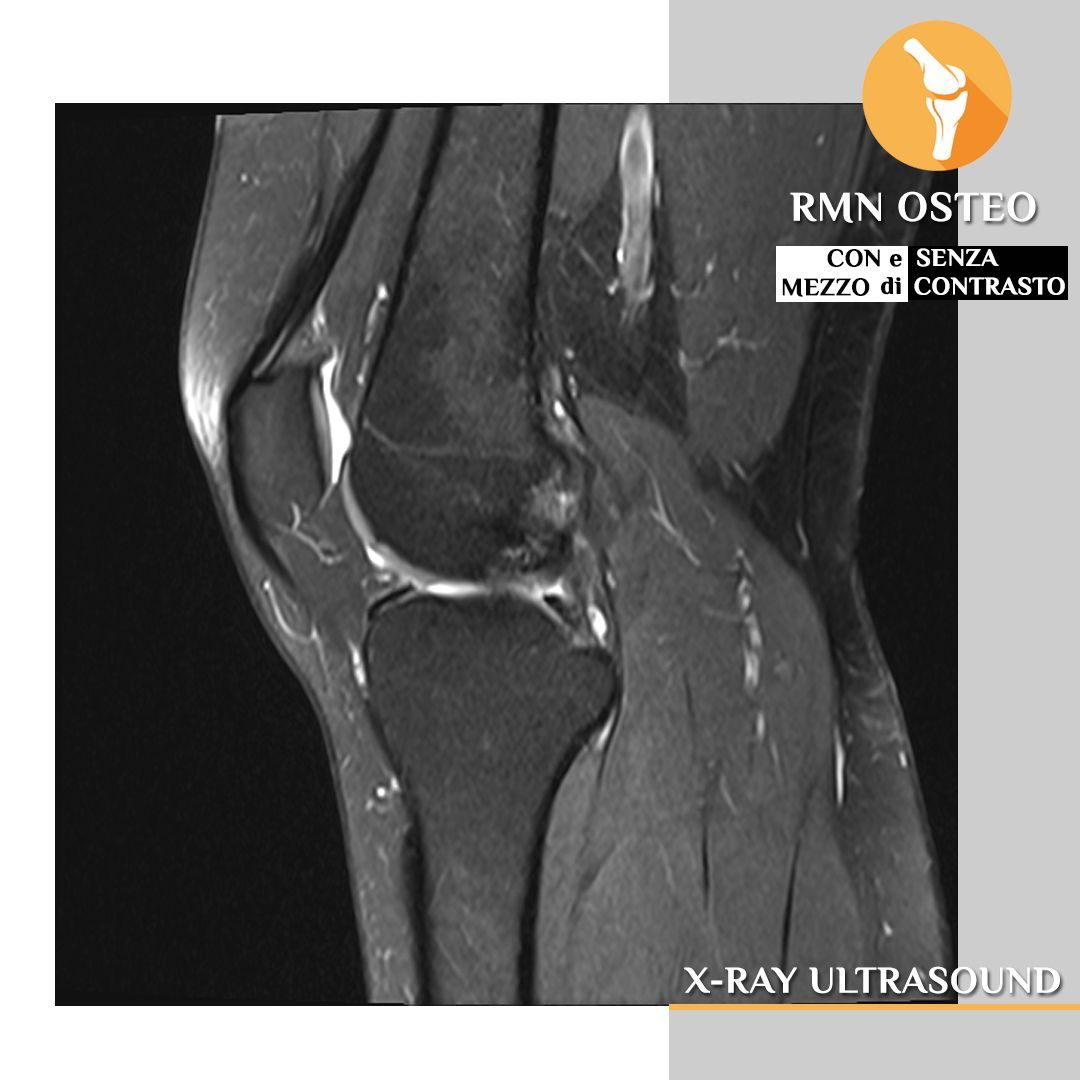

Diagnosi di patologie complesse: la risonanza Magnetom Altea è particolarmente indicata per la diagnosi di patologie complesse di diverse aree del corpo, tra cui:

- Osteoarticolare: ossa, articolazioni, legamenti, tendini